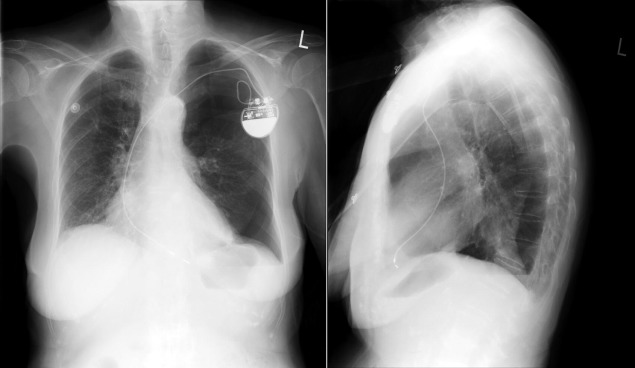

Chest radiography has a standard role in the identification of several potential complications such as pneumothorax, hemothorax, and several forms of malposition after insertion of pacemakers, implantable cardioverter defibrillators (ICDs), and cardiac resynchronization therapy devices.

Pacemaker leads are apparent, and ICDs are more obvious because of their larger coils. Coronary sinus leads for cardiac resynchronization therapy are finer leads.

Endocardial Pacer Leads

The position and integrity of endocardial pacer leads should be verified, especially when pacemaker dysfunction is clinically suspected ( Graphics 23-1 to 23-4 ; Figs. 23-1 to 23-15 ).The most common cause of pacemaker dysfunction that is apparent on the chest radiography is distal lead displacement/misplacement.

With a right atrial lead , the tip should be in the right atrial appendage.

With a right ventricular lead , the tip should lie anteriorly at the apex of the heart.